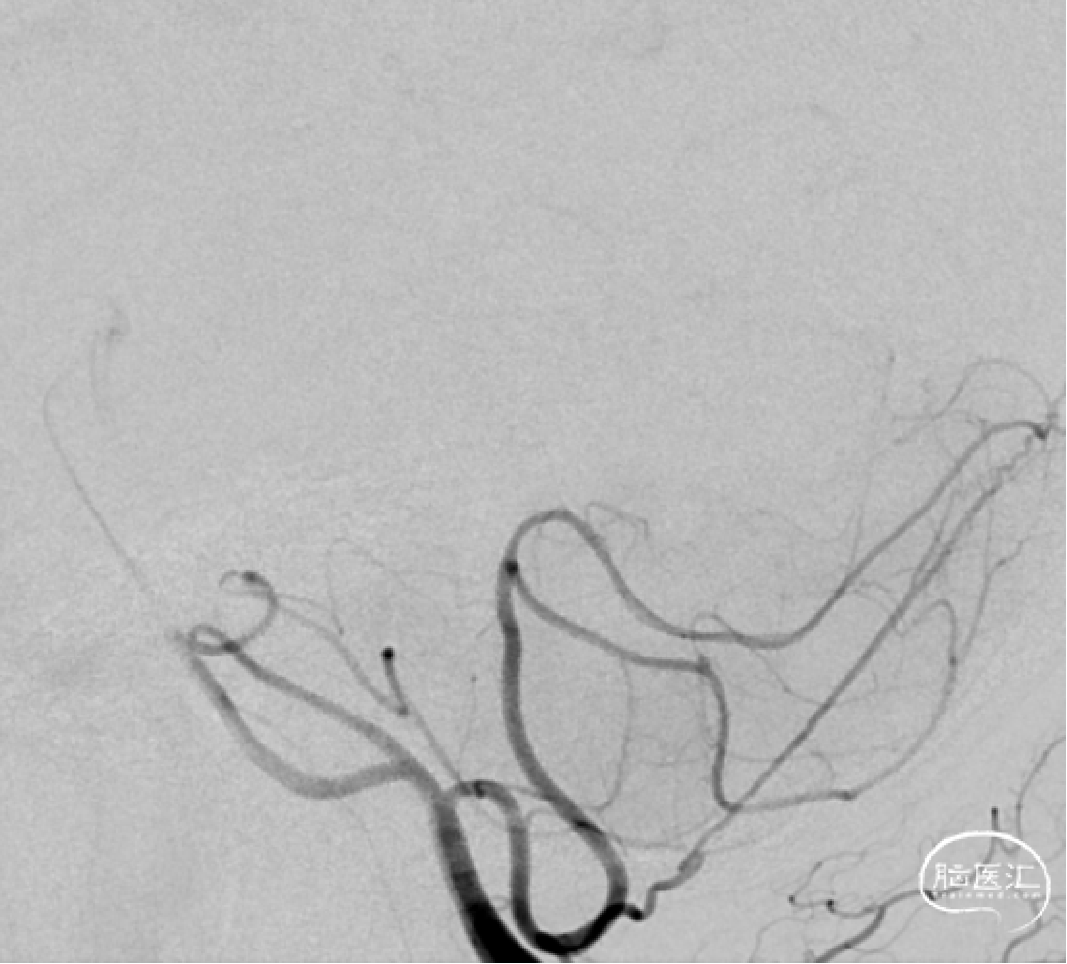

➢DSA(2023.11.10)

R-DAS技术超选右侧颈内,右侧颈内动脉血管迂曲。

颅内球囊 2.25*15mm扩张,扩张至10个atm。

狭窄改善。